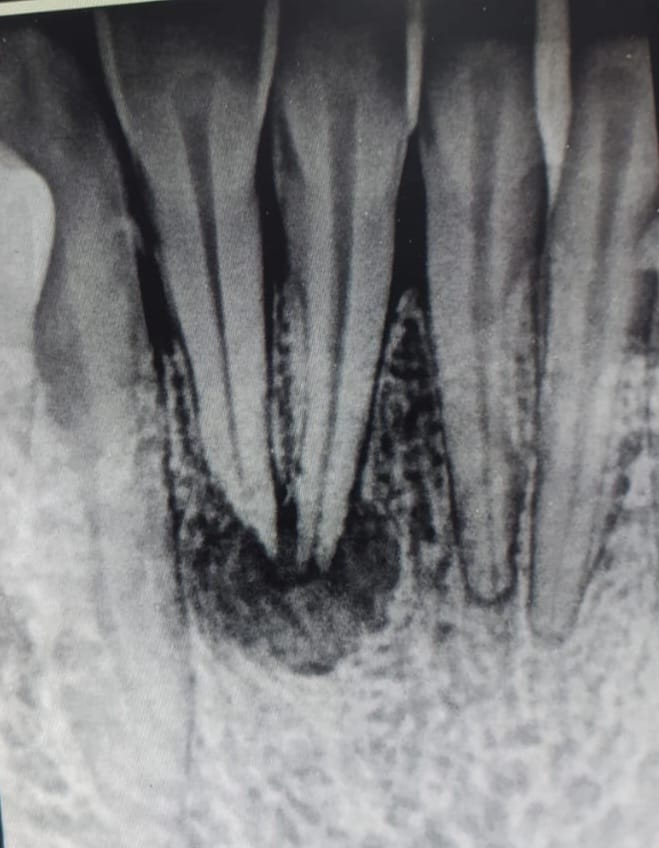

Published October 2, 2023 at 659 × 848 in Effects of Betel Nut Chewing on Dental Health.

Radiograph showed well demarcated radiolucency involving apex of tooth no.41,42